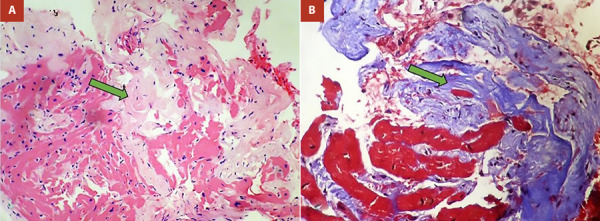

心内膜肌纤维化或戴维斯病是一种罕见的限制性心肌病的原因。它的特点是纤维物质沉积在心内膜,导致快速进行性心力衰竭。它最常影响两个心室,孤立地累及右心室是最不常见的形式。该疾病的临床表现以右心衰症状为基础,但也可能出现心律失常和传导障碍。治疗是由充血的管理和有症状患者的手术干预决定的。我们提出了第一例分离自哥伦比亚右心室的心内膜肌纤维化,我们描述了临床,病因学,影像学和管理特点,以便向医学界提供对这种疾病的大致理解,重点是一种不寻常的表现方式。

Endomyocardial fibrosis or Davies disease is a rare cause of restrictive cardiomyopathy. It is characterized by the deposit of fibrous material in the endocardium that leads to quickly progressive heart failure. It most frequently affects both ventricles, with isolated involvement of the right ventricle being the least common form. The clinical presentation of this entity is based on symptoms of right heart failure, although arrhythmias and conduction disorders may also be present. The treatment is determined by the management of congestion and surgical intervention in symptomatic patients. We present the first case of endomyocardial fibrosis isolated from the right ventricle in Colombia, we describe the clinical, etiological, imaging and management characteristics in order to deliver to the medical community an approximate understanding of this disease focusing on an unusual way of presentation.